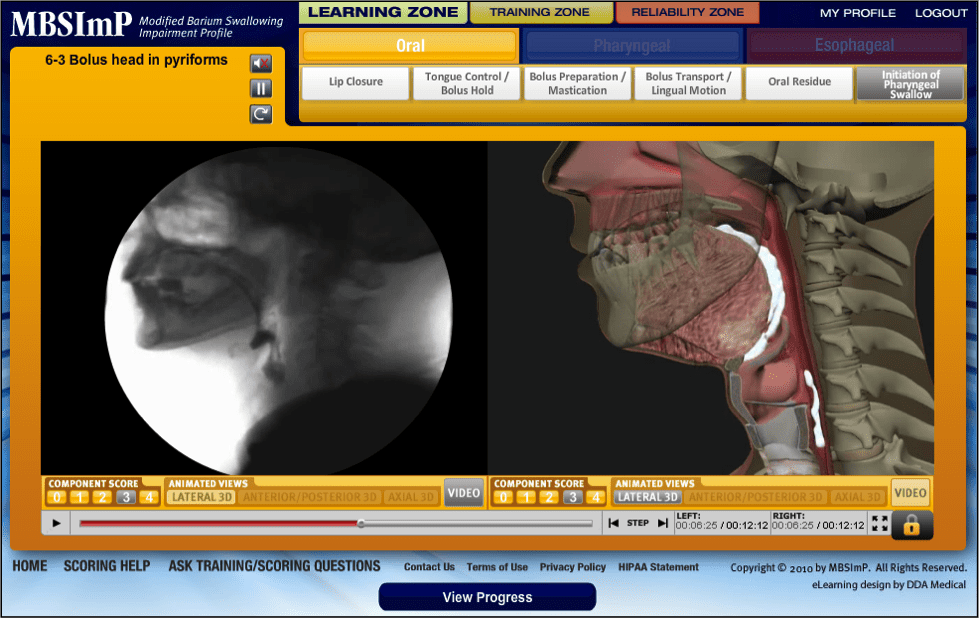

MBSImP Bonnie Martin-Harris